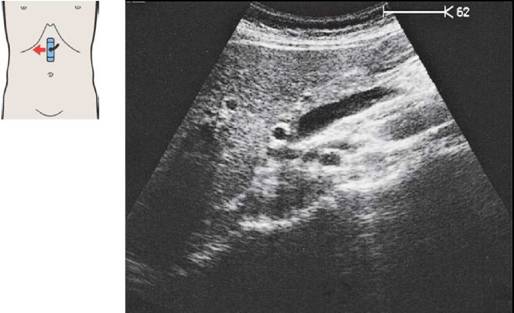

39 Место впадения почечной вены

27 Почечная вена

Правая почечная артерия и вена при поперечном сканировании

В большинстве случаев место впадения правой почечной вены в нижнюю полую вену визуализируется отчетливо.

При последовательном поперечном сканировании нижней полой вены можно наблюдать, как почечная вена отделяется от нее и направляется в сторону почки.